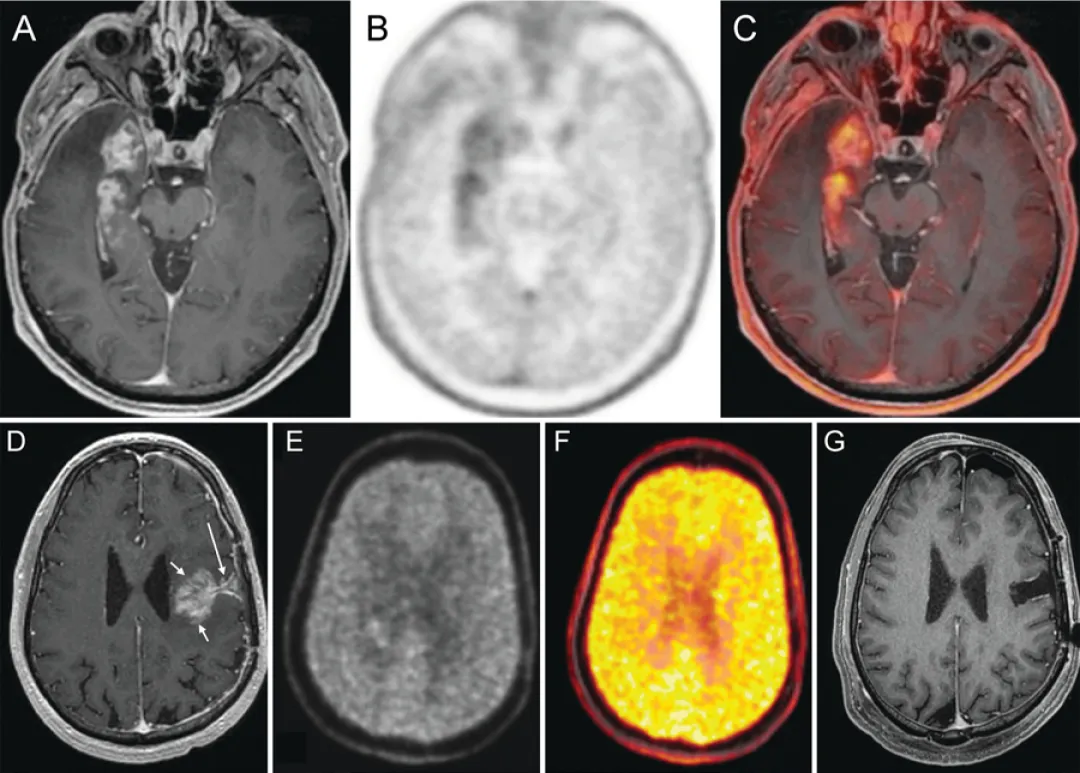

正电子发射断层扫描已成为另一种重要的影像学手段,其通过使用放射性标记的氨基酸示踪剂(如O-(2-[¹⁸F]氟乙基)-L-酪氨酸、3,4-二羟基-6-¹⁸F-氟-L-苯丙氨酸或¹⁸F-氟代脱氧葡萄糖;图5)来识别代谢活跃的肿瘤区域。该技术基于肿瘤细胞糖酵解过程中代谢活性增强及氨基酸摄取增加的特性。由于脑部PET扫描存在本底活性低的固有局限性,FET可能优于FDG。最新研究不仅支持FET的高敏感性与特异性,还证实其能准确指导治疗决策,FDOPA在诊断性活检中同样具有价值。

图5.PET在复发判断中的应用案例

A-C:右颞叶GBM放疗后6个月

A:轴位T1增强MRI显示右内侧颞叶占位性强化。B:轴位FDOPA PET显示右颞区代谢摄取增高。C:轴位FDOPA PET-MR融合图像精确显示代谢活性定位于右内侧颞叶占位

D-G:左额叶复发性GBM再程放疗联合免疫治疗后2个月

D:轴位T1增强MRI显示手术切缘深部(长箭头)类肿块强化灶(短箭头),基于此影像行再次切除。E:轴位FDOPA图像显示强化灶内无摄取增高。F:轴位FDOPA伪彩图显示强化灶内无摄取增高。G:再次切除术后1月轴位T1增强MRI显示无残留强化